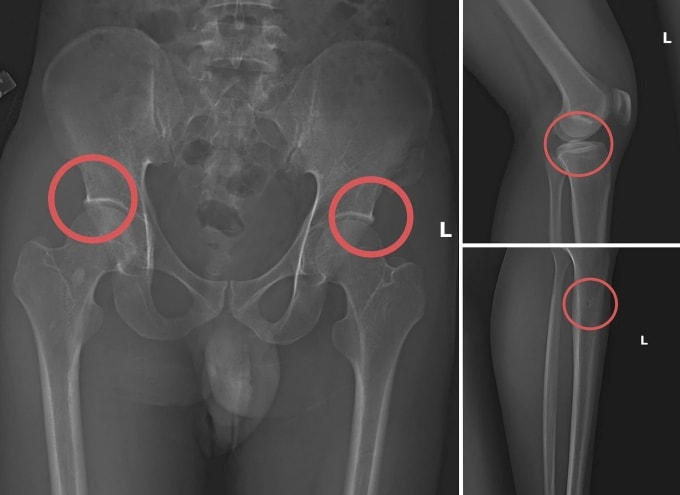

Châu trực tiếp thực hiện hành vi tiêm thuốc mê rồi dùng kim tiêm, búa đinh để tác động vào xương người mua bảo hiểm. Sau khi can thiệp đã tạo nên các vết nứt, vỡ xương giống hệt bị tai nạn thật. Tạo thương tích xong, anh ta tiếp tục hướng dẫn đồng phạm dựng hiện trường giả như điện giật ngã, trượt chân ngã suối nhằm hợp thức hóa bệnh án và hoàn thiện hồ sơ yêu cầu chi trả.

Công an Phú Thọ đánh giá, đường dây này hoạt động có tổ chức, tinh vi nhằm qua mặt cảnh sát. Thủ đoạn "tàn nhẫn, vô nhân tính, coi thường sức khỏe, tính mạng của người tham gia". Chúng đã lên kế hoạch, tính toán kỹ để gây thương tích đúng vị trí có mức chi trả cao, khiến các công ty bảo hiểm khó phát hiện dấu hiệu gian dối.